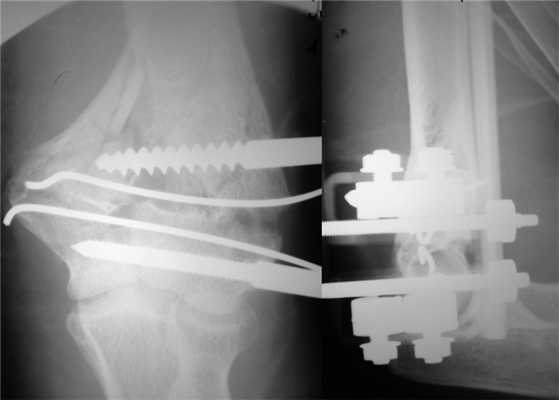

На следующий день под новокаиновым блоком плечевого сплетения произведена операция: закрытая репозиция и чрескостный остеосинтез левой плечевой кости спице-стержневым аппаратом внешней фиксации конструкции А.И. Городниченко. Через разрезы кожи и мягких тканей по наружной поверхности левого плеча длиной до 5 мм введено 2 кортикальных стержня в диафиз плечевой кости, один кортикальный и один спонгиозный стержень и 2 спицы с упорной площадкой в мыщелки и надмыщелки плечевой кости. После фиксации проксимальных стержней в аппарате под контролем электронно-оптического преобразователя произведена закрытая репозиция с помощью съемных рукояток с последующей стабилизацией дистальных стержней и спиц (рис. 3). Рисунок 3. Рентгенограммы больной П. после остеосинтеза левой плечевой кости спице-стержневым аппаратом. Кожа вокруг стержней ушита одиночными швами. Кровопотеря в ходе операции 20 мл. Продолжительность операции 40 мин.

Послеоперационное течение без осложнений, проводили регулярные перевязки с обработкой кожи вокруг стержней и спиц растворами антисептиков и сменой асептических повязок. Швы вокруг стержней сняты через 8 дней после операции, пациентка выписана на амбулаторное лечение с рекомендациями по дальнейшему восстановительному лечению. Движения в левом локтевом суставе перед выпиской из стационара показаны на рис. 4. Рисунок 4. Рентгенограммы больной П. после остеосинтеза левой плечевой кости спице-стержневым аппаратом.